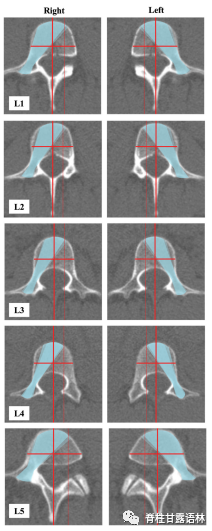

研究人员从“癌症影像档案”(The Cancer Imaging Archive, TCIA)在线数据库中随机抽取51例患者的CT扫描进行分析。使用Sectra 3D Spine软件创建3D渲染图,放置虚拟螺钉并进行测量。在每个腰椎,绘制左右椎弓根通道。在每个椎弓根处模板化两个螺钉位置,“内侧限制螺钉”(MLS)和“外侧限制螺钉”(LLS)。每个限制螺钉都是螺钉在不引起内侧或外侧骨折的情况下可以存在的最极端位置。安全区域定义为MLS和LLS之间的区域。测量每个水平(L1和L5之间)左右两侧的安全区域。

内外侧限制螺钉的限定和安全区的描绘

腰1-5椎体双侧安全区的绘制